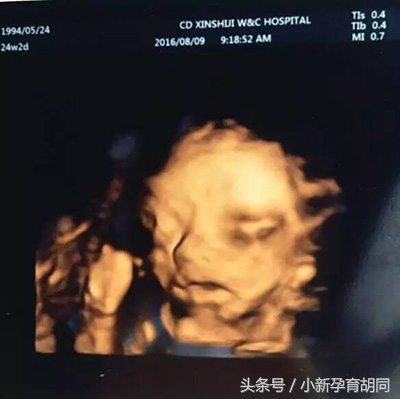

一直期待的四维,儿子超级配合。但拿到照片瞬间懵逼了。这是我儿子吗?为什么那么丑。(当时一直不知道是儿子,从一开始就想要妹妹。看到这张大饼脸我整个人都快不好了)有种累觉不爱的感觉,怀疑这是不是我亲儿子。

朋友安慰我说四维照不准,慢慢的也就自我催眠了可能长大点30周的时候就好了吧。

小伙子你这个时候真的好丑,妈妈要存下来给你未来媳妇儿留个纪念。看她以后会不会和我一样嫌弃这个时候的你。